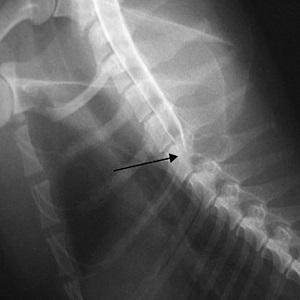

Подозрение на перелом подтверждается с помощью рентгенографии или магнитно-резонансной томографии (МРТ).

Причины перелома могут быть разнообразными: это не только прямые удары, полученные во время спортивных занятий или в результате ДТП, но и чрезмерные сгибания и разгибания шеи.

Например, резкие движения при копке земли лопатой, когда позвоночник постоянно сгибается и разгибается, могут привести к перелому остистого отростка. В момент сгибания на позвоночник оказывается дополнительная нагрузка.